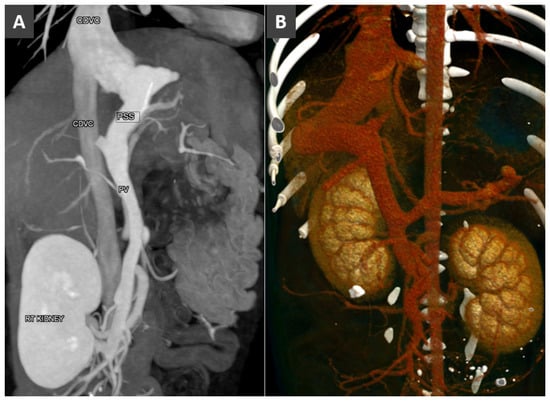

Congenital Portosystemic Shunt

3.8. Porto-Portal Collaterals or Cavernous Transformation of the Portal Vein